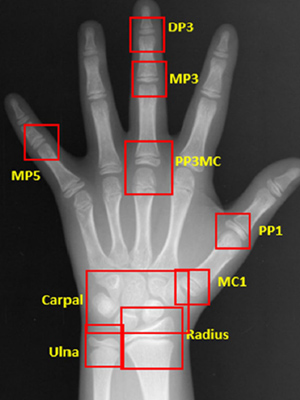

AI 기반 정밀 성장판 검사

이지민 대표원장이 공동 연구한 AI 기반 성장판 분석 논문의 학술적 근거를 바탕으로,

정밀 성장판 검사 프로그램을 통해 성장기 아동의 성장 페이스를 정확히 예측하고

최적의 교정 시기와 치료 계획을 설계합니다.

소아청소년기의 정상적인 성장 여부 판단을 위해

손뼈 엑스레이를 분석하여

높은 정확도의 골연령 판독 결과를 제시합니다.

엑스레이 판독 결과와 키와 몸무게 등의

환자 정보를 함께 평가하여 환자의 예상 신장을 비롯한

유용한 성장 정보를 담은 리포트를 제공합니다.